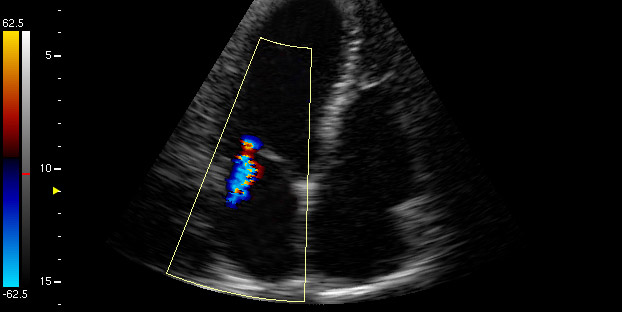

При любых жалобах на работу сердечно-сосудистой системы пациенту необходимо пройти стандартные обследования. В первую очередь это электрокардиограмма (ЭКГ) и ультразвуковое исследование сердца (кардио-скопия). Эти методы доступны в большинстве многопрофильных медицинских учреждений и играют ключевую роль в диагностике сердечных заболеваний. Например, на ЭКГ можно выявить признаки гипертрофии левого предсердия (Р-mitrale — расширенный и раздвоенный зубец Р) и гипертрофии других отделов сердца, что может указывать на прогрессирование болезни.

На ультразвуковом исследовании сердца врач определит степень митральной регургитации, оценит увеличение сердечных камер и общую сократительную функцию миокарда.